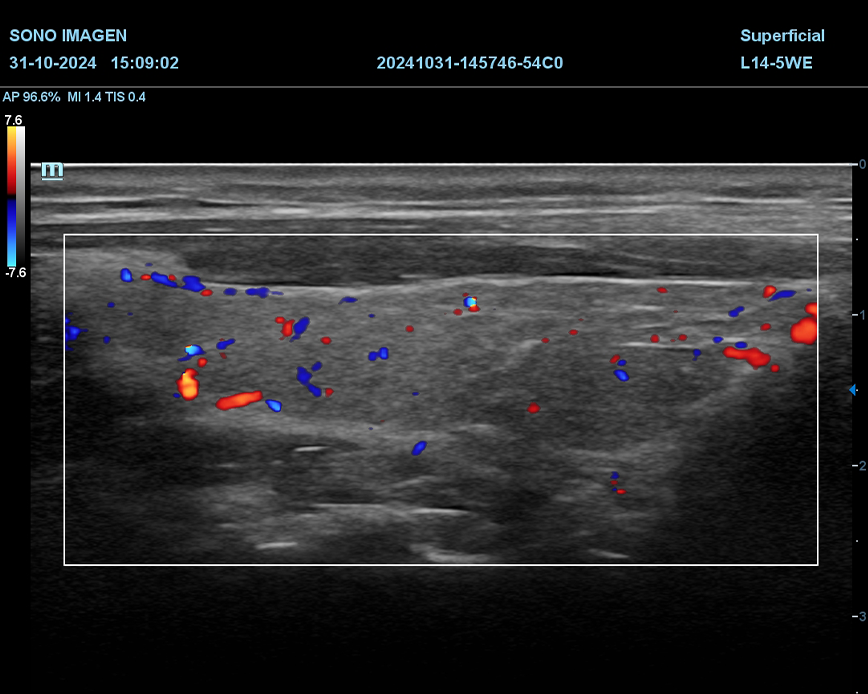

Ecografía Prostática

- hiperplasia prostática benigna(HPB)

- cáncer de próstata

- prostatitis

- dificultad para orinar o retención urinaria

- hematuria

- alteraciones en la fertilidad masculina

- control postquirúrgico o postratamiento

- anomalías detectadas en estudios previos

- quistes prostáticos